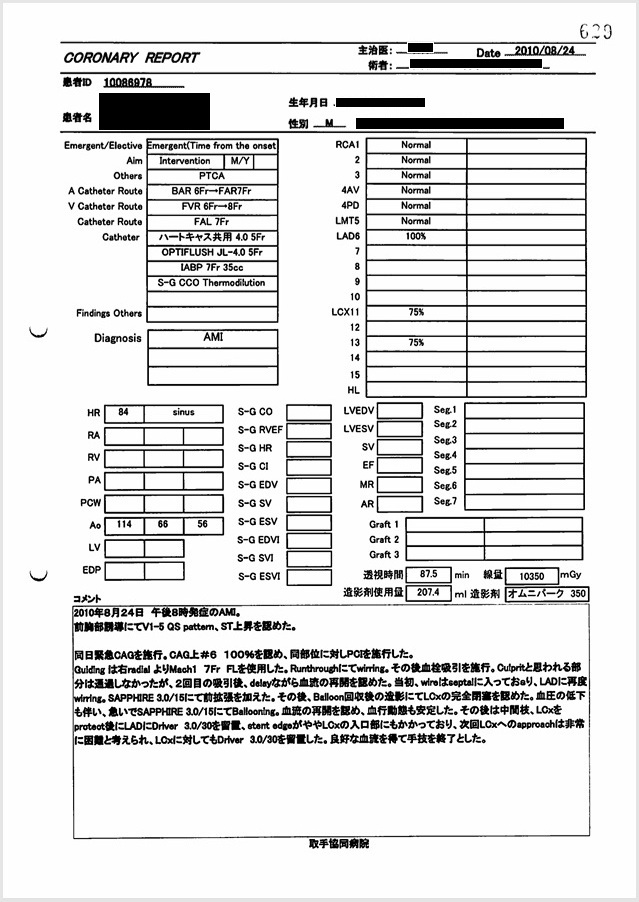

- 8月24日:右橈骨動脈からアプローチするも失敗。右大腿動脈からアプローチやり直し

カテーテル治療は22時35分に開始され、右橈骨動脈を穿刺し開始されたが冠動脈へのアプローチに失敗し、右大腿動脈からやり直しとなっている。

証拠: 下記レポートに「右raアプローチできず変更」の記載あり。「ra」とはradial(橈骨動脈)のこと。

- 8月24日~25日:カテーテル手技の大事故(冠動脈損傷・閉塞・穿孔)

左前下行枝穿孔、左冠動脈主幹部解離・閉塞、大動脈損傷の痕跡。

証拠:PCI動画からの抜粋

救命のためには心臓血管外科での緊急手術が必要だが、医師らはその手配をせず放置し、談笑していた。 - 8月24日~25日:過剰放射線量

心カテ検査記録によると、PCIでの放射線被曝量は10350mGyに達し、許容量を大幅に超過。

証拠:PCIレポート

22時35分に開始され、右橈骨動脈にガイドワイヤーを挿入して手技が開始されたが、 冠動脈にアプローチできず、右大腿動脈から挿入された。その間、アプローチが失敗した時間帯のPCI画像が 存在せず、ここで大事故を起こした証拠であるこの間の画像が抜き取られた可能性が疑われる。 PCIは3時間と長時間を要し、その間の放射線被曝量も人体に深刻な影響を与えるほど大量であった。 PCIの動画を確認すると左冠動脈主幹部閉塞・損傷・解離、左冠動脈前下行枝近位部・遠位部の穿孔、 左回旋枝への血栓閉塞など多数の致命的な手技ミスが認められた。 救命のためには心臓血管外科での開胸手術が必要のはずであったが、医師はPCI終了後、遺族に対して「治療は無事成功した」としてこの手技ミスを隠蔽し、心臓血管外科への手配をせずに放置し談笑していた。